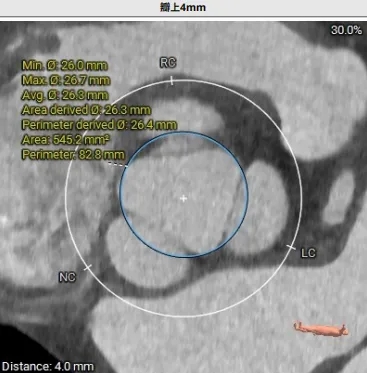

瓣上结构测量

周长77.3 周长径24.6

周长82.8 周长径26.4

周长92.8 周长径29.5

周长98.2 周长径31.3